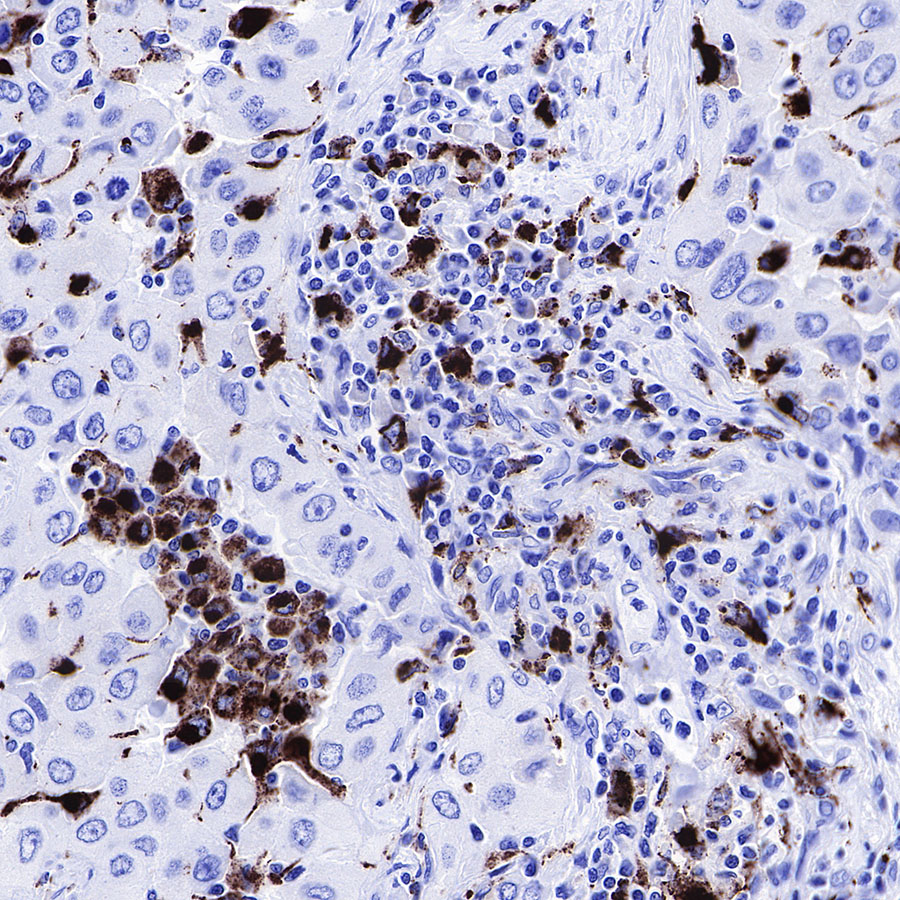

IHC shows positive staining in paraffin-embedded human lung adenocarcinoma. Anti-CD68 antibody was used at 1/1000 dilution, followed by a HRP Polymer for Mouse & Rabbit IgG (ready to use). Counterstained with hematoxylin. Heat mediated antigen retrieval with Tris/EDTA buffer pH9.0 was performed before commencing with IHC staining protocol.